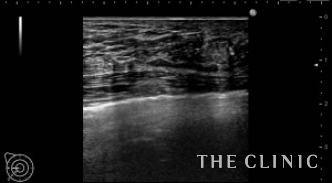

しこりは消失しました。